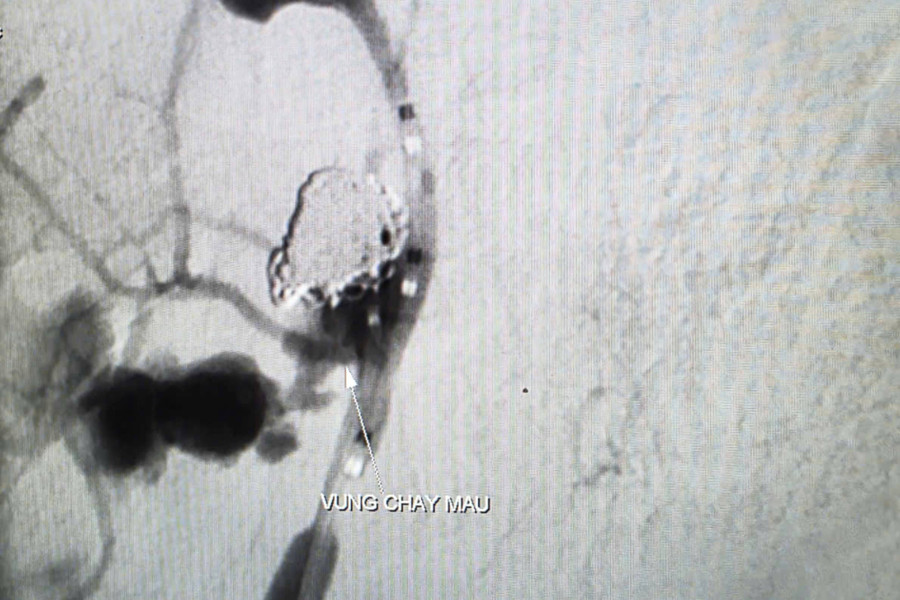

vom-hau-1.jpg

Hình ảnh thoát mạch trước can thiệp. Ảnh: BVCC

Trước nguy cơ mất máu ồ ạt, các bác sĩ quyết định thực hiện chụp và can thiệp cầm máu dưới máy chụp mạch số hóa xóa nền (DSA). Thủ thuật do BS.CKII Trần Công Khánh, Phó Trưởng khoa Chẩn đoán hình ảnh, cùng ê-kíp thực hiện.

Kết quả ghi nhận ổ giả phình động mạch cảnh trong phải đoạn cổ dưới nền sọ, kích thước 4,2x4,8mm, cổ túi phình rộng và đang chảy máu.